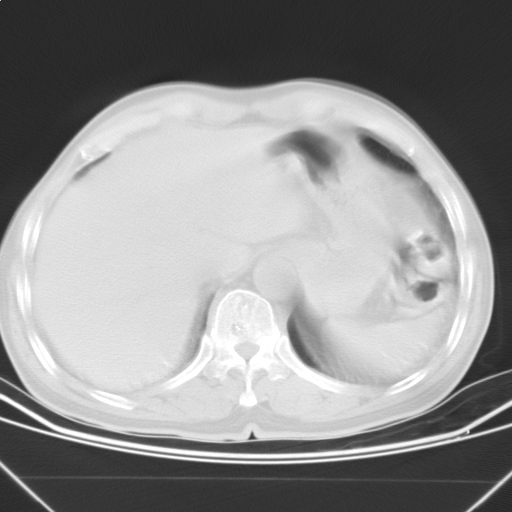

以下是引用随光逐影在2009-5-1 13:53:00的发言:[br]考虑为:1)两肺血行播散型肺结核;2)右肺下叶炎症感染。3)右侧胸膜增厚。